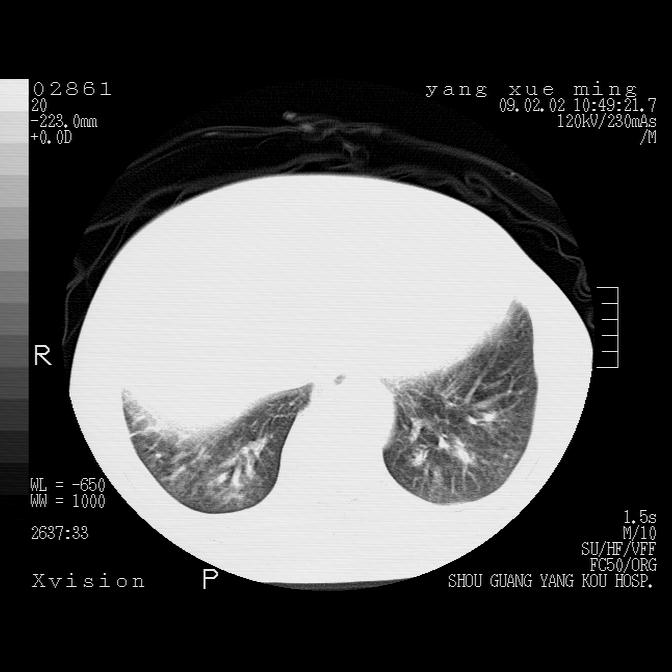

以下是引用zbp537在2009-2-3 19:08:00的发言:[br]我诊断为肺泡性肺水肿。[br]诊断依据:[br]1、心影普遍增大,肺血管增粗,并见絮状高密度影,肺门改变显著。[br]2、临床上表现胸闷咳嗽,无发烧,不是一个典型的肺部感染的病史。

以下是引用lkc8963在2009-2-3 20:11:00的发言:[br]1)右上肺陈旧病灶。2)右下肺团块及团片影,影像表现符合感染。3)左心增大,左冠脉钙化,符合冠心病。4)双侧肺门扩大,以左侧为著,肺动脉干略粗,左上肺局限性气肿,为谨慎起见,需除肿瘤,建议增强。

以下是引用lkc8963在2009-2-3 20:11:00的发言:[br]1)右上肺陈旧病灶.2)右下肺团块及团片影,影像表现符合感染.3)左心增大,左冠脉钙化,符合冠心病.4)双侧肺门扩大以左侧为著,肺动脉干略粗,左上肺局限性气肿,为谨慎起见,需除肿瘤,建议增强.